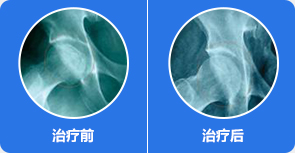

治疗前:股骨头塌陷明显,骨质受损严重,关节间隙变窄

治疗中:股骨头受损骨质开始自我修复,关节间隙逐渐正常

治疗后:股骨头骨质修复完整,关节间隙正常